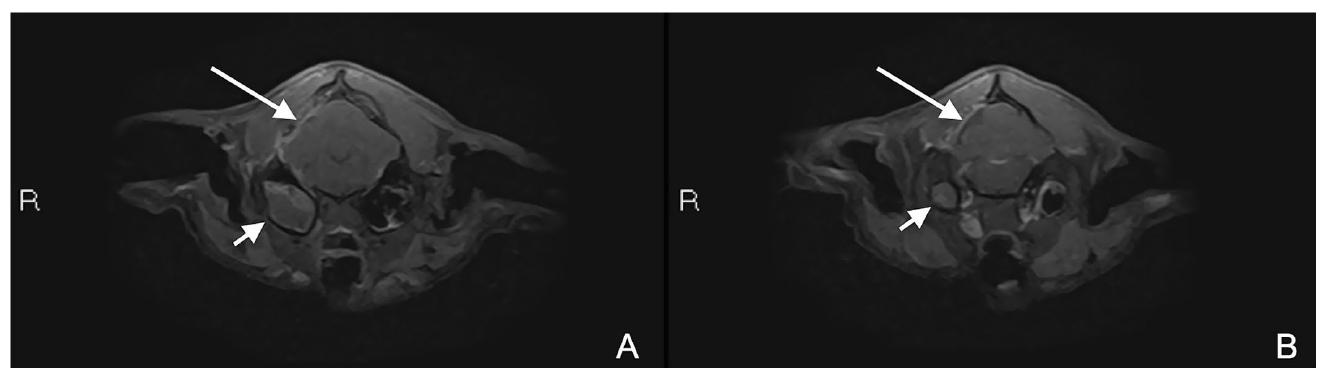

↑ 术后两个月的MRI检查。增强后T1W脂肪抑制轴位图像(AB)显示与区域脑膜增厚和强化(长白色箭头)相关的术后改变,以及右侧中耳炎的进展(短白色箭头)。

这些发现支持右侧颞肌局部炎症、区域脑膜增厚和增强(提示局部脑膜炎)、小的浅表小脑实质缺损伴轻度液体积聚(信号强度与脑脊液等同),与之前脑外病变部位的获得性脑积水一致,右侧中耳炎显著进展(下图)以及左侧中耳炎的早期阶段。

↑ 术前(A)和术后两个月的MRI检查(B)。增强后T1W背侧图像(AB)显示右侧中耳炎进展(短白色箭头)和疑似左侧早期中耳炎(B,长白色箭头)。